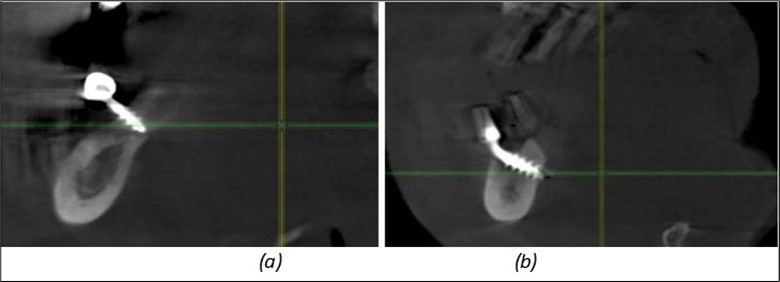

Figure 11.Implants in the anterior area anchored in the nasal cortex (BCS and TPG): (a), (c) – BCS implants fixed in the nasal cortex; (b), (d) – TPG implants fixed in the second nasal cortex with compression in the trabecular area.

Figure 12.Implants fixed distally in quadrant 4 with fixation at the level of the mylohyoid line: (a) The most distal implant fixed in unaffected bone from the previous restoration; (b) The implant fixed in the area where the two stage implant was removed.